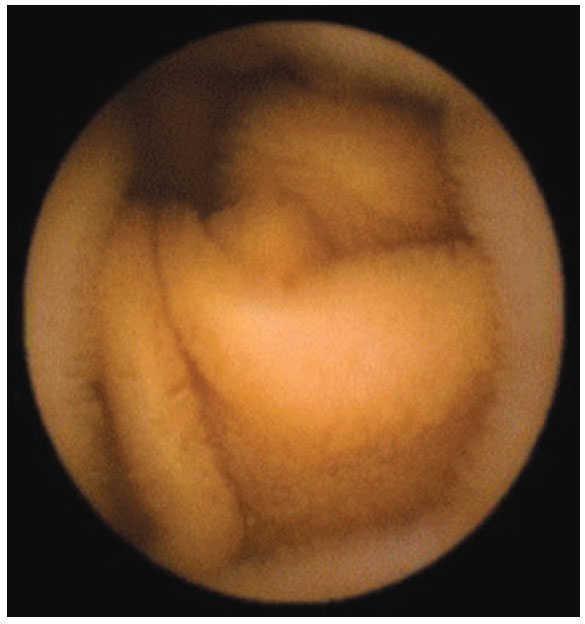

ResultadosEn el periodo comprendido entre enero 2003 a marzo 2008 se realizaron un total de 45 estudios. En 43 pacientes, la cápsula fue deglutida con agua, en dos de ellos tuvo que ser introducida con sobretubo, debido a la incapacidad de los pacientes para deglutirla; procedimientos que se realizaron sin complicaciones y con éxito. El sexo femenino predominó con 27 pacientes (60%) con una mediana de edad de 58.16 años, con intervalo entre los 18 y 84 años. El grupo etáreo más afectado fue el comprendido entre los 71 a 84 años de edad con 14 casos. El motivo de envío más frecuente fue el sangrado gastrointestinal de origen oscuro, con 32 casos (71.11%). Los siguientes fueron diarrea crónica con cinco casos (11.11%), dolor abdominal tres casos (6.67%) y melena tres casos (6.67%). Los hallazgos reportados incluyeron: Sin causa 18 casos (40%), erosiones en 10 casos, algunas de ellas relacionadas con AINE (22.20%) (figura 2). Alteraciones vasculares en ocho casos (17.76%), pólipos en seis casos (13.32%), gastropatía nodular con dos casos (4.44%), tumoraciones en dos casos (4.44%) (figuras 3 y 4), y con un caso (2.22%) cada una de las siguientes patologías: pseudopoliposis antral, diverticulosis y sangrado activo en el Treitz de causa no determinable. En general, el procedimiento fue bien tolerado. No se presentaron complicaciones durante ni posterior al procedimiento. No se reporta en ningún caso la retención de la cápsula en el tubo digestivo. Mención aparte, aunque no fue motivo del presente estudio, será importante contar con el número de pacientes que fueron sometidos a estudios complementarios (serologías, enteroscopias, laparotomías, etc.), ya que con ello se podrán tener más argumentos para definir el lugar que actualmente ocupa la videocápsula en nuestro país y tal vez con más investigación de este tipo, poder sugerir un algoritmo de estudio para pacientes con hemorragia de origen oscuro.

Figura 4. Causa de hemorragia gastrointestinal de origen oscuro e intususcepción.